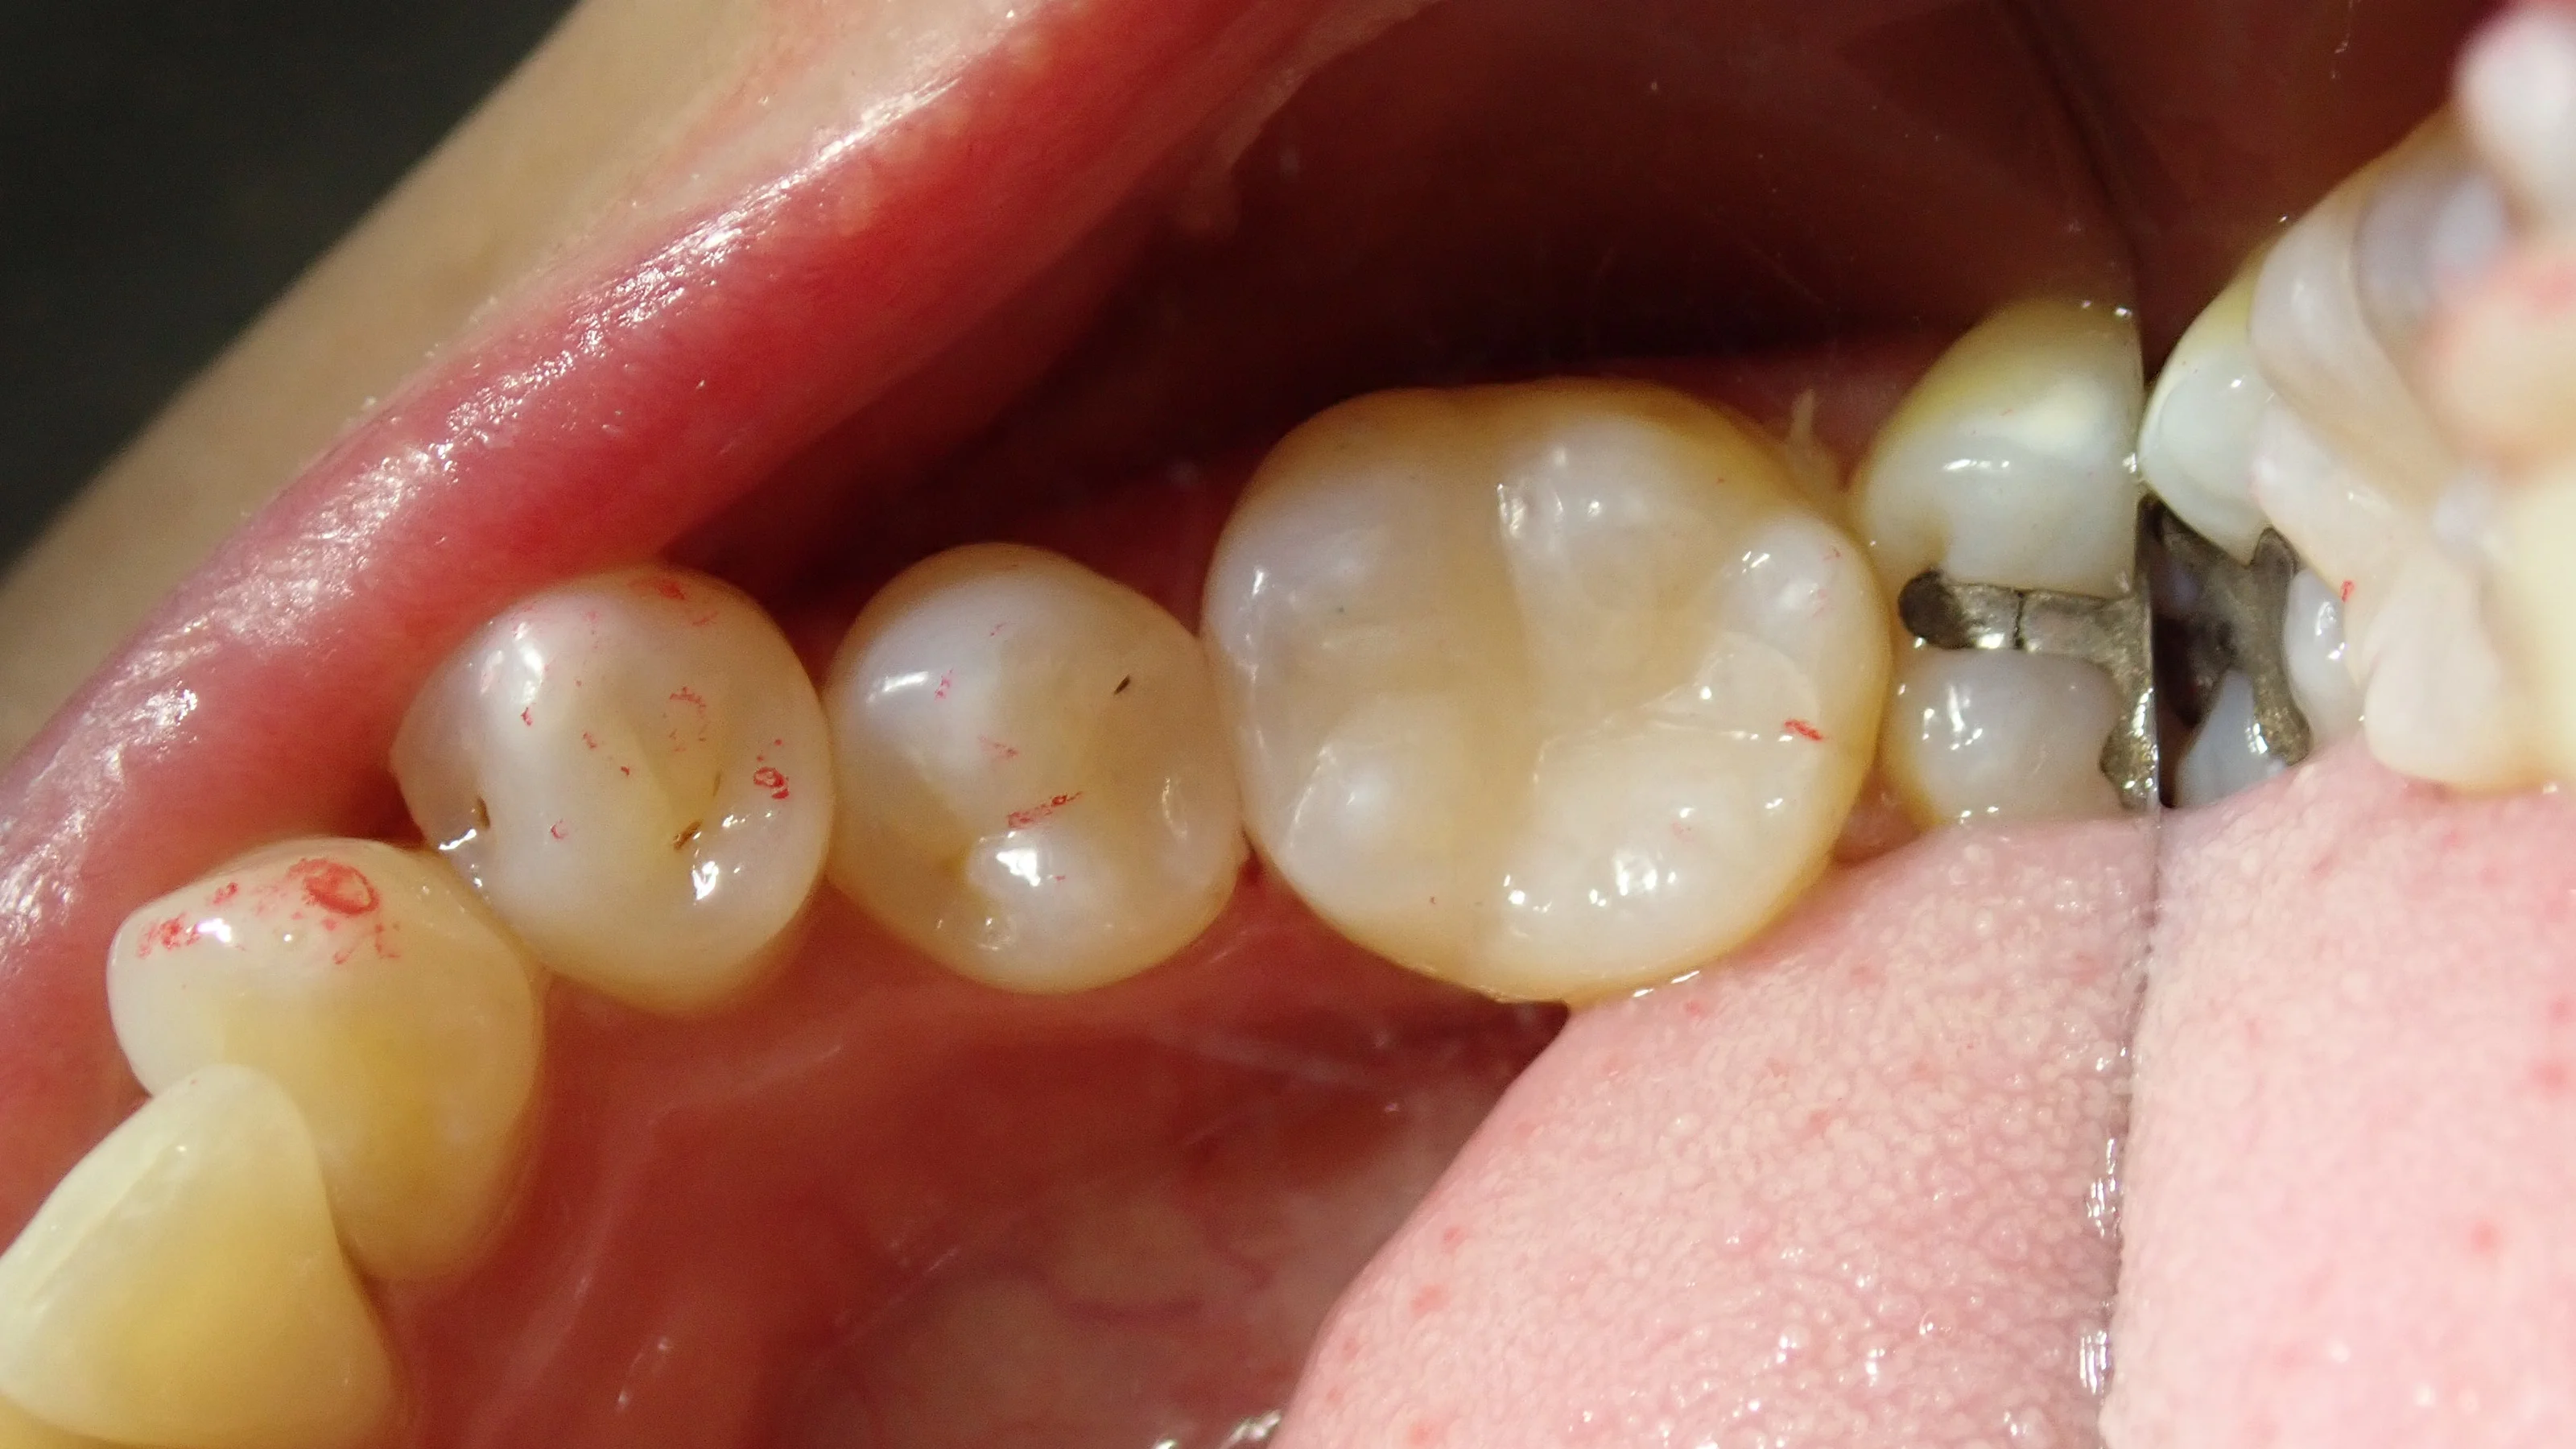

そして、こちらが虫歯を取りきった状態。

歯の色が随分と綺麗になっているのが分かるかと思います。

歯との間に虫歯があったので、そちらも一緒に除去しました。

そしてこれが、詰め終わった状態です。

ある程度色もしっかりと合っているかと思います。

コンポジットレジンはこの歯の溝を再現するかどうかも結構意見が分かれてきますが、私は、食べ物を綺麗に排出するためにも必要な構造だと思ってますので、なるべく再現するようにはしています。

平なコンポジットレジン=粗悪ってことはないので、その点は安心してくださいね。